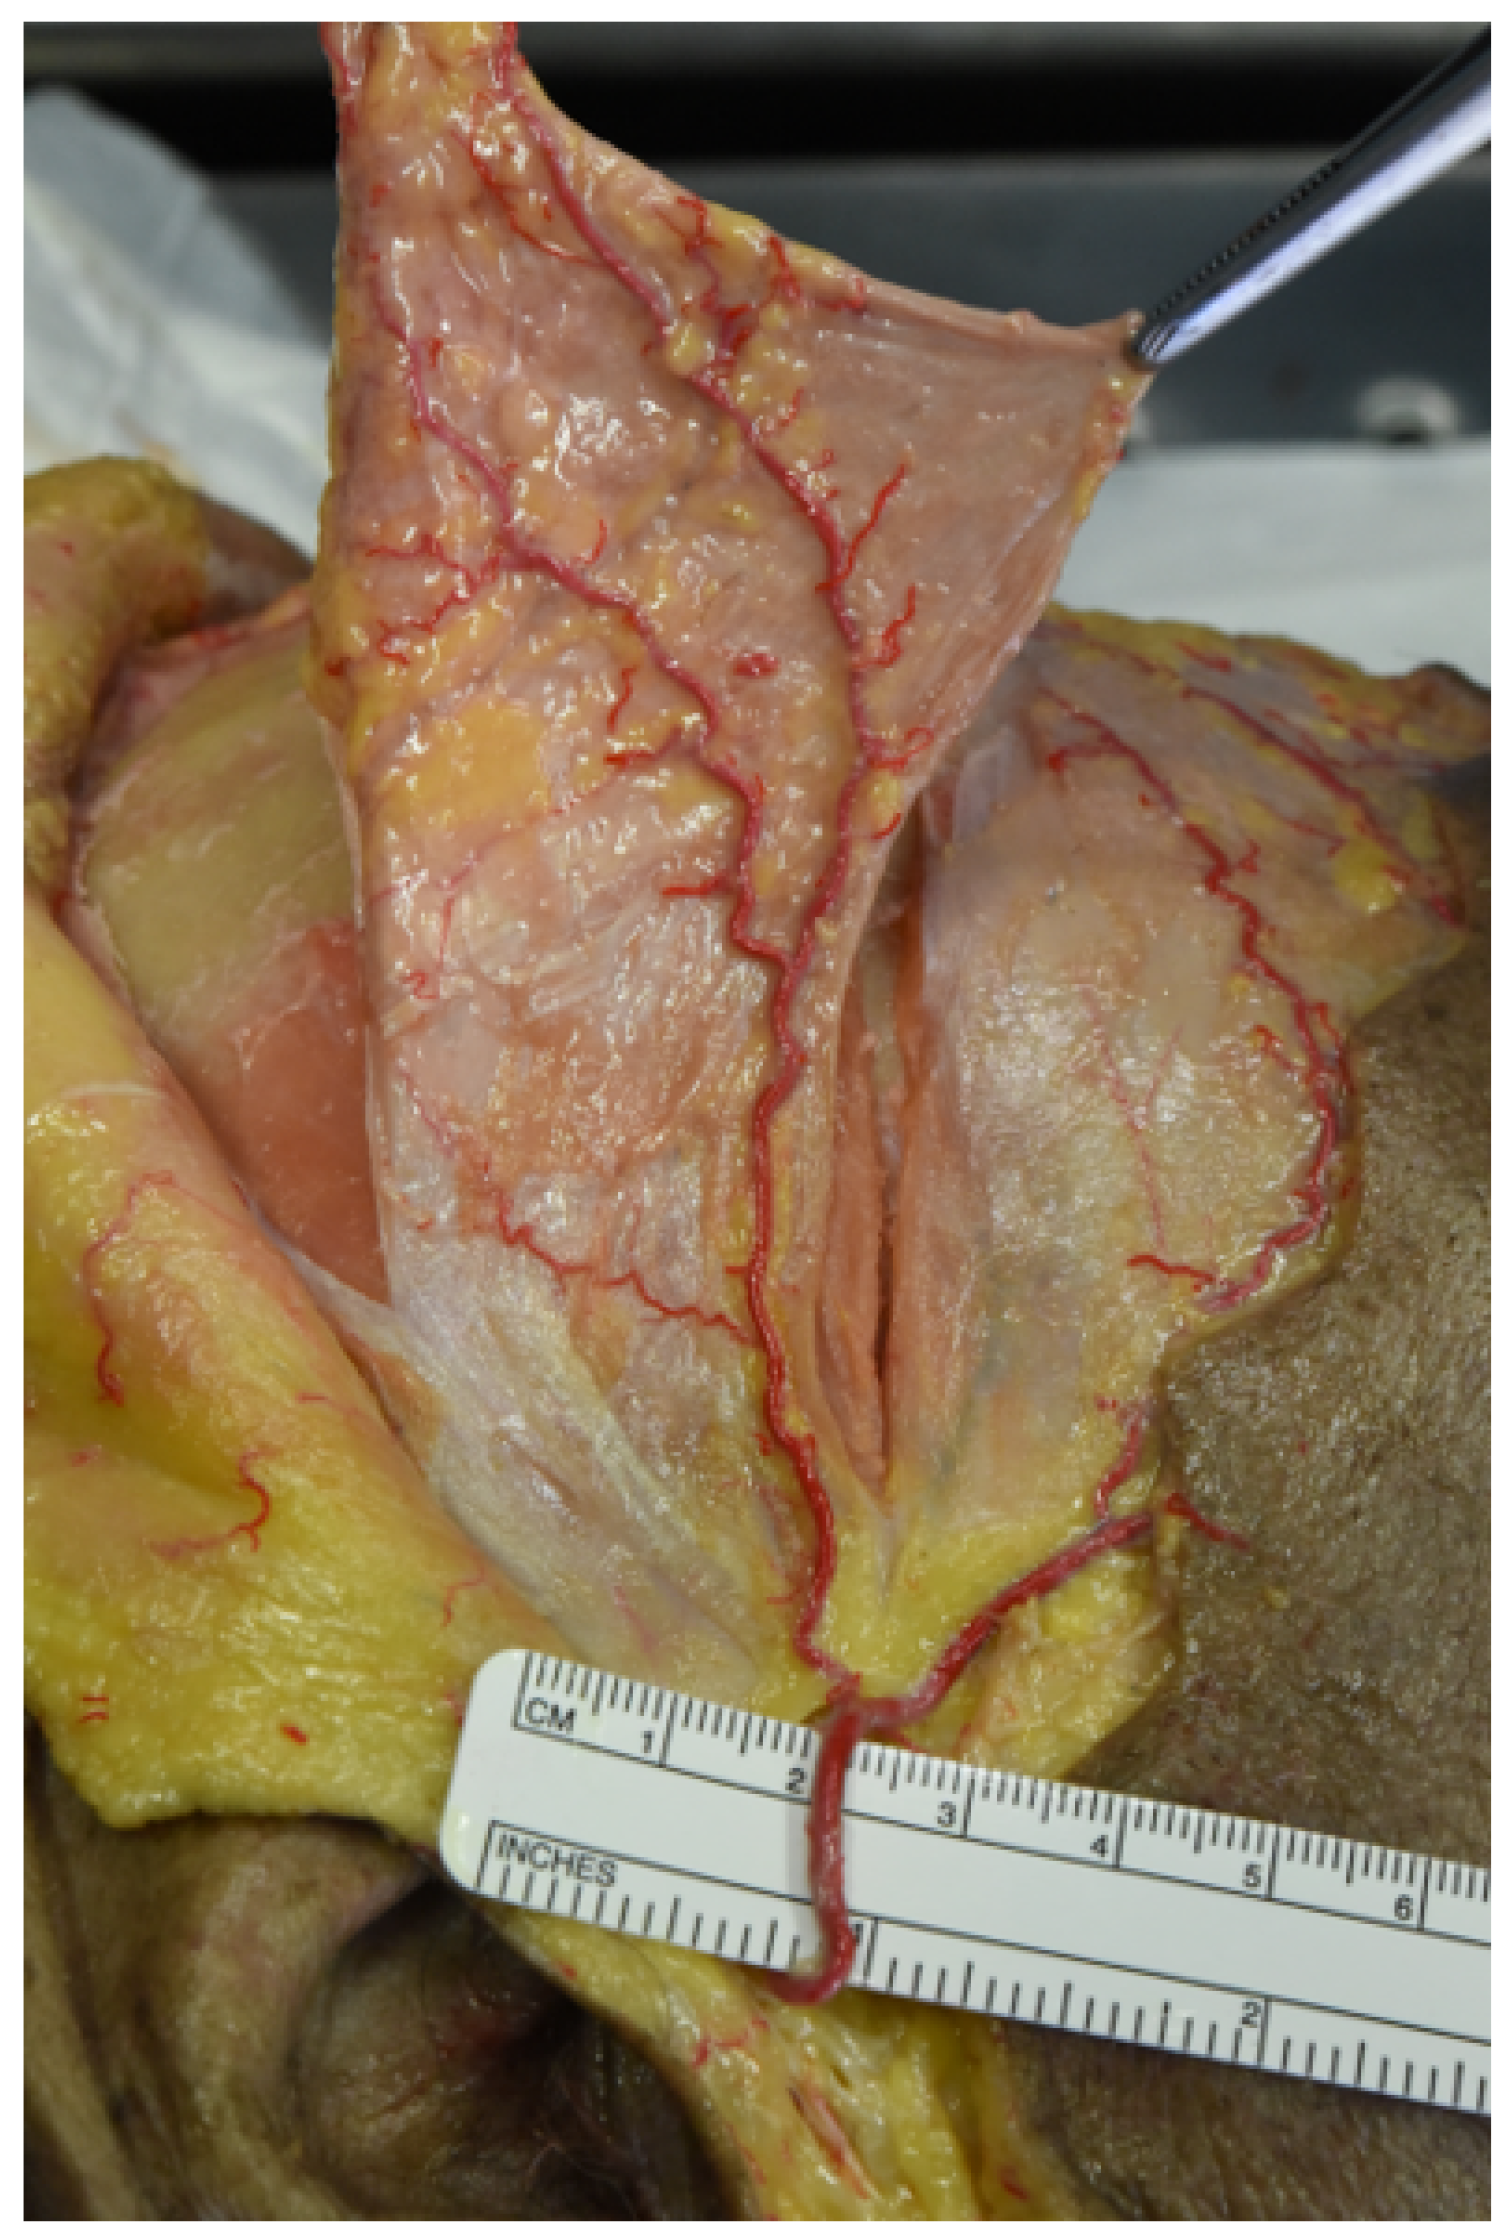

During dissection, perforating vessels arising from the superficial temporal network and nourishing the pericranium were identified in each specimen. These vessels seemed to pass through the galea aponeurotica until they reached the deeper pericranial layer. As a matter of fact, these are fundamental for the vitality of the flap; injuring these vessels could compromise the engraftment of the flap to the recipient site (Figure 3).

Figure 3. Perforating vessels to the pericranium. The figure shows perforating branches of the superficial temporal artery observed during dissection, nourishing both the galeal and pericranial layer.